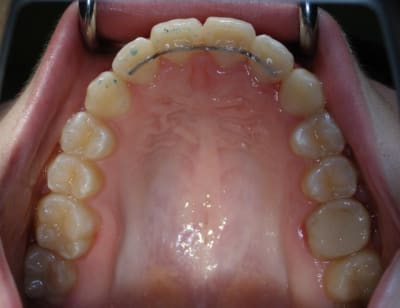

Ma contention...fil plat tréssé 8 brins...33€ les 10 brins de 10 cm... pas cher donc et taux de satisfaction "perso" de 99,99%. Du faite du plat du fil, la couche de composite peut-être réduite au minimum.